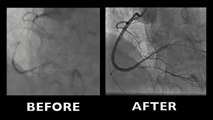

Interventional cardiology encompasses a variety of procedures applying to the treatment of coronary and peripheral vascular diseases as well as cardiac functional and structural impaired conditions. All of the techniques and devices used are extremely specialized; they require particular skills that can directly impact on the outcome of the treatment.

Our faculty and guests share their knowledge and expertise via documented HD videos to help you understand the procedures, use the devices, assess the immediate results, and prevent or avoid pitfalls. All the steps of the procedures are explained, including screening, selection and preparation of the patients, device preparation and delivery, anesthesia, medication, tips and tricks, and a lot more.